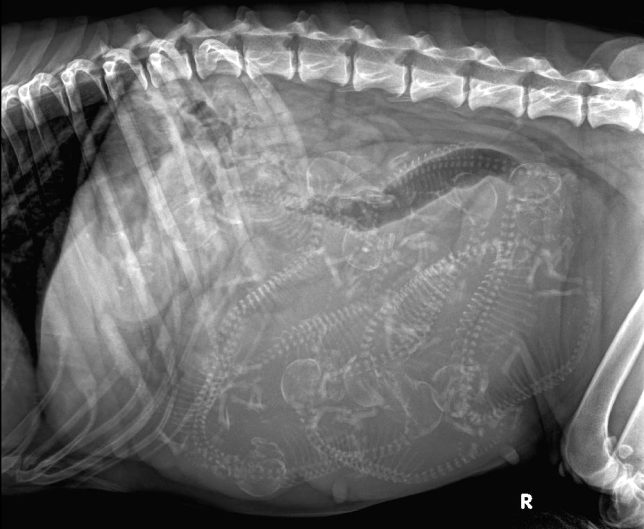

Do porodu štěňátek zbývají poslední dny. Aike vše snáší velice dobře a zvyká si na porodní bednu.

RTG snímek 54. den – bříško plné štěňátek 🙂